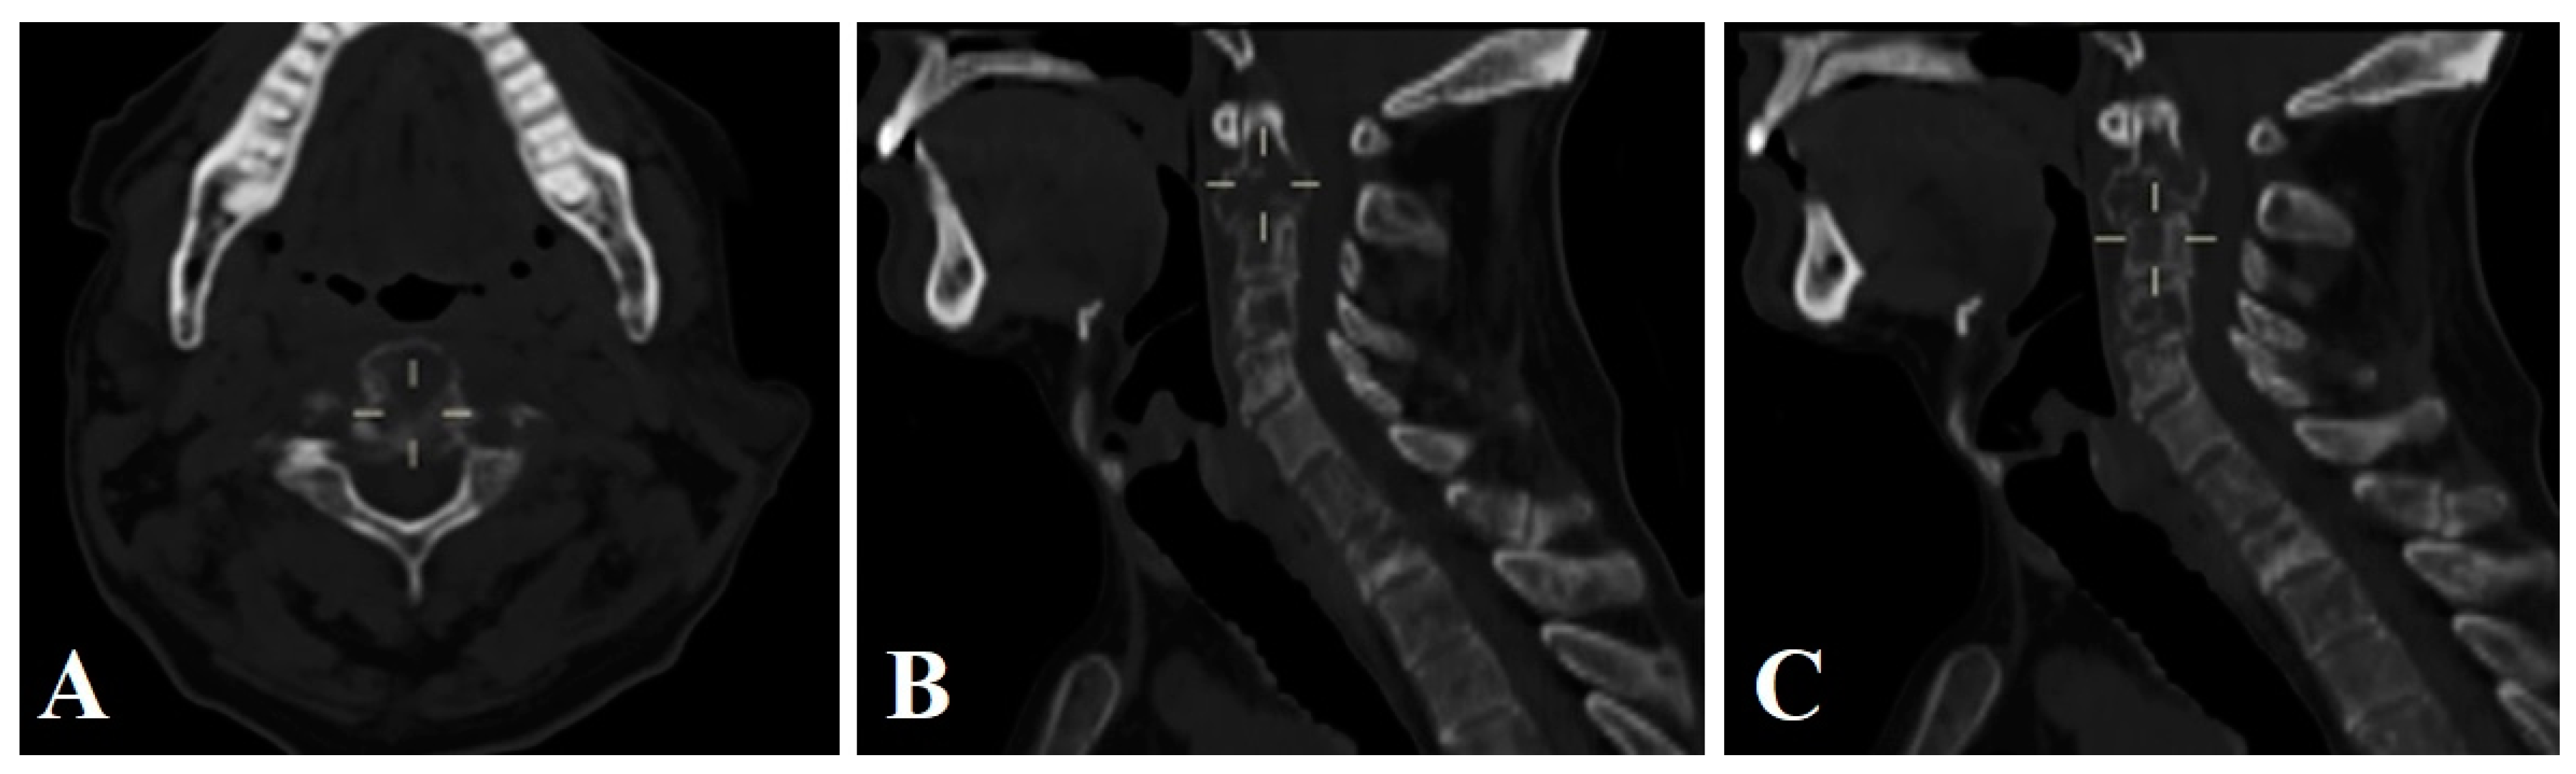

3.1.2. Clinical Case 2

3.1.3. Clinical Case 3

3.3. Surgical Technique and Radiological Follow-Up